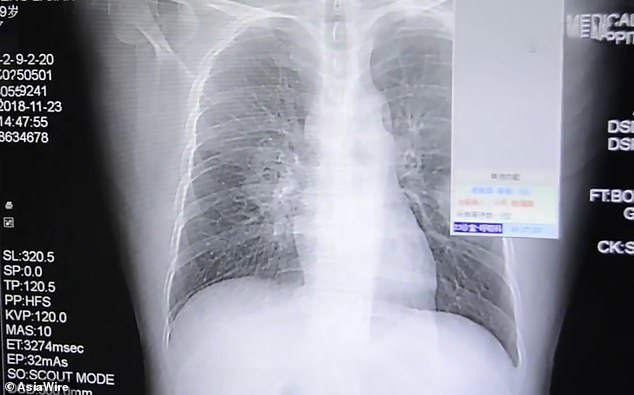

Mới đây bệnh viện 909 ở thành phố Chương Châu, tỉnh Phúc Kiến, Trung Quốc đã tiếp nhận một trường hợp khá đặc biệt, bệnh nhân 37 tuổi họ Bành nhập viện trong tình trạng ho nhiều và liên tục kêu đau ngực.

Sau khi tiến hành chụp X-quang, các bác sĩ kết luận người đàn ông này bị nhiễm nấm phổi mức độ nghiêm trọng. Theo một nghiên cứu được công bố trên trang Science Direct, nhiễm nấm phổi là tình trạng sức khỏe nguy hiểm có thể dẫn đến tử vong nếu không phát hiện và điều trị kịp thời.

Điều khiến các bác sĩ băn khoăn là loại nấm mà bệnh nhân hít phải phát triển nhiều trong tất và giày. Khai thác lời kể của bệnh nhân, mọi băn khoăn đã được giải đáp, theo người đàn ông họ Bành, hàng ngày anh thường có thói quen cầm đôi tất đã đi cả ngày của mình và cho lên mũi để ngửi. Từ thông tin trên, các bác sĩ khẳng định rằng sở thích có phần khác người kia chính là nguyên nhân khiến phổi của anh bị nhiễm trùng.

Được biết trước đó, họ Bành thường xuyên phải thức khuya để chăm sóc con nên không được nghỉ ngơi đây đủ, điều đó làm cho hệ thống miễn dịch của anh cũng yếu đi nhiều. Đó là lí do khiến nấm và vi khuẩn trong tất càng dễ dàng tấn công và phát triển thành bệnh.

Bệnh nhân ngay lập tức được nhập viện để tiến hành điều trị. Theo các bác sĩ, dự kiến khả năng phục hồi của họ Bành sẽ tương đối nhanh.